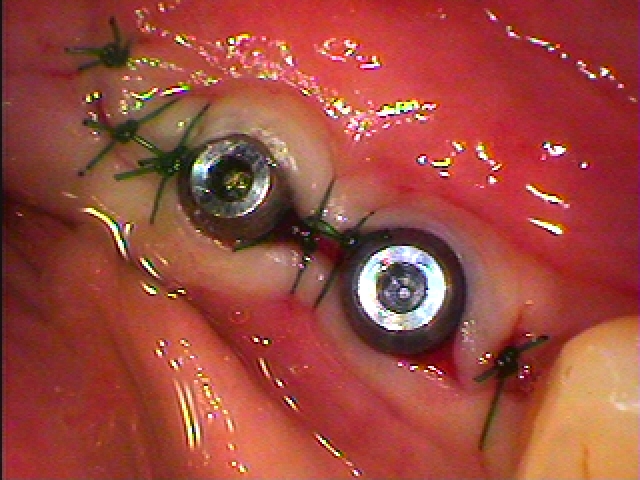

縫合して終了となります